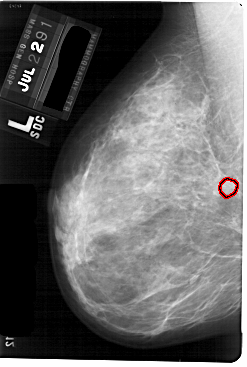

A_1757_1.LEFT_MLO

LEFT_MLO LINES 5491 PIXELS_PER_LINE 3691 BITS_PER_PIXEL 12 RESOLUTION 43.5 OVERLAY

FILE: A_1757_1.LEFT_MLO.OVERLAY

TOTAL_ABNORMALITIES 1

ABNORMALITY 1

LESION_TYPE MASS SHAPE ROUND MARGINS OBSCURED

ASSESSMENT 3

SUBTLETY 3

PATHOLOGY BENIGN

TOTAL_OUTLINES 1

BOUNDARY